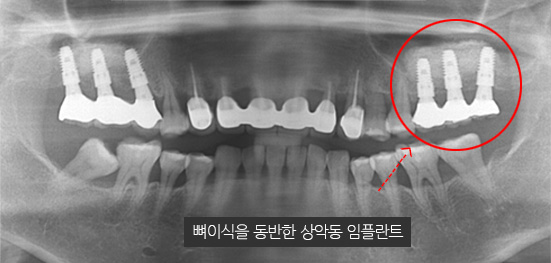

위 턱뼈는 아래턱뼈보다 얇고 코와 뺨 사이 빈 공간(상악동)이 있어서 임플란트를 식립할 경우 실패 가능성이 높아집니다. 상악동거상술이란 임플란트 수술방법을 시행할 때 노하우가 부족하면 임플란트 식립 후 임플란트가 빠져버리거나 입 천장 쪽에 구멍(천공)이 나는 부작용이 생기기 때문에 치과치료 중 가장 어려운 수술 중 하나 입니다.

부족한 잇몸 뼈를 보충하는 뼈 이식술과 난이도 높은 상악동거상술을 진행해 안정적인 임플란트 수술을 마쳤습니다.

고운미소치과에서는 턱뼈의 해부학적 구조를 충분히 고려하고 임플란트 수술을 해온 노하우를 바탕으로 상악동 거상술은 물론 난이도가 높은 수술을 안정적으로 진행하고 있습니다.

잇몸 뼈가 녹아내려 임플란트 12개 진단을 받고 내원한 환자, 고운미소에서 치주치료를 시행한 결과 전치부 잇몸이 개선되어 발치 하지 않고 크라운으로 수복하였고, 어금니는 상악동거상술 후

6개의 임플란트를 식립하였습니다.

잇몸 염증으로 치조골 손실이 많은 상태

잇몸 건강이 회복된 앞니는 크라운으로 수복